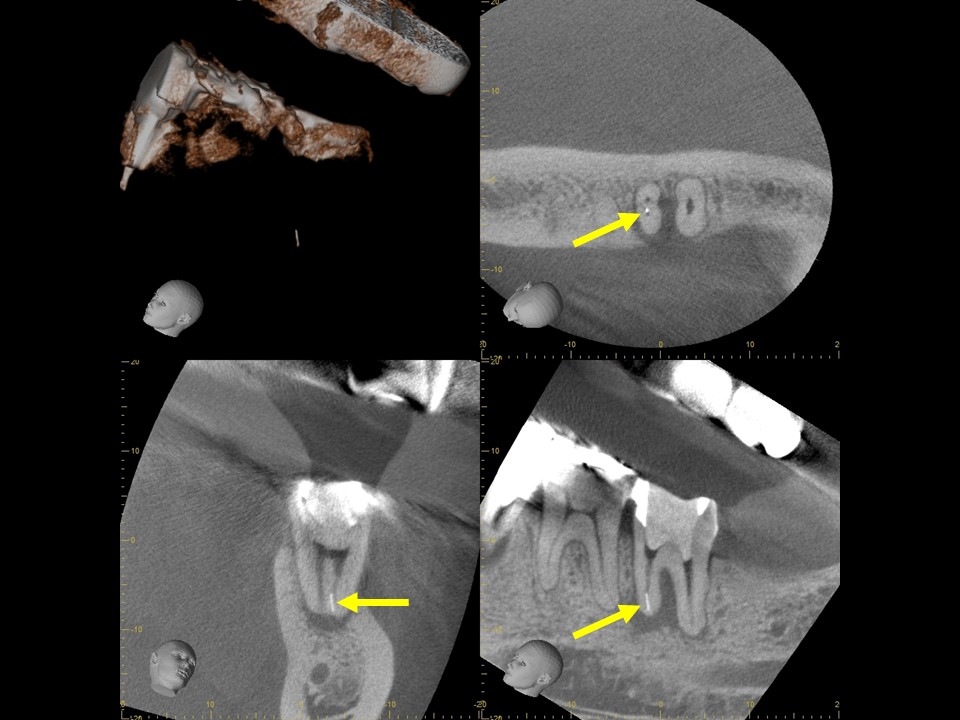

診断と治療計画の立案

当該の左下7番の奥歯はクラウンで被せてありましたが、頬側に歯茎の腫れ(フィステル、サイナストラクト)を認めました。レントゲンおよびCTによる診査を行ったところ、すでに根管治療が施してあるものの根管充填が不十分で、根尖病変を生じていました(下写真)。また、歯根の先端部分にはファイルと思われる器具の破折片を認めました(矢印)。根管内部へのバクテリアの感染による慢性化膿性根尖性歯周炎と診断し、再根管治療をおこなうことにしました。

治療前レントゲン | 治療前CT |

治療前レントゲン |

治療前CT |

治療前のレントゲンおよびCT画像です。当該歯はすでに根管治療が施してあり、根尖部には根尖病変によるX線透過像を認めます。

また、根尖部にはファイルと思われる器具の残存を認めます(矢印)。